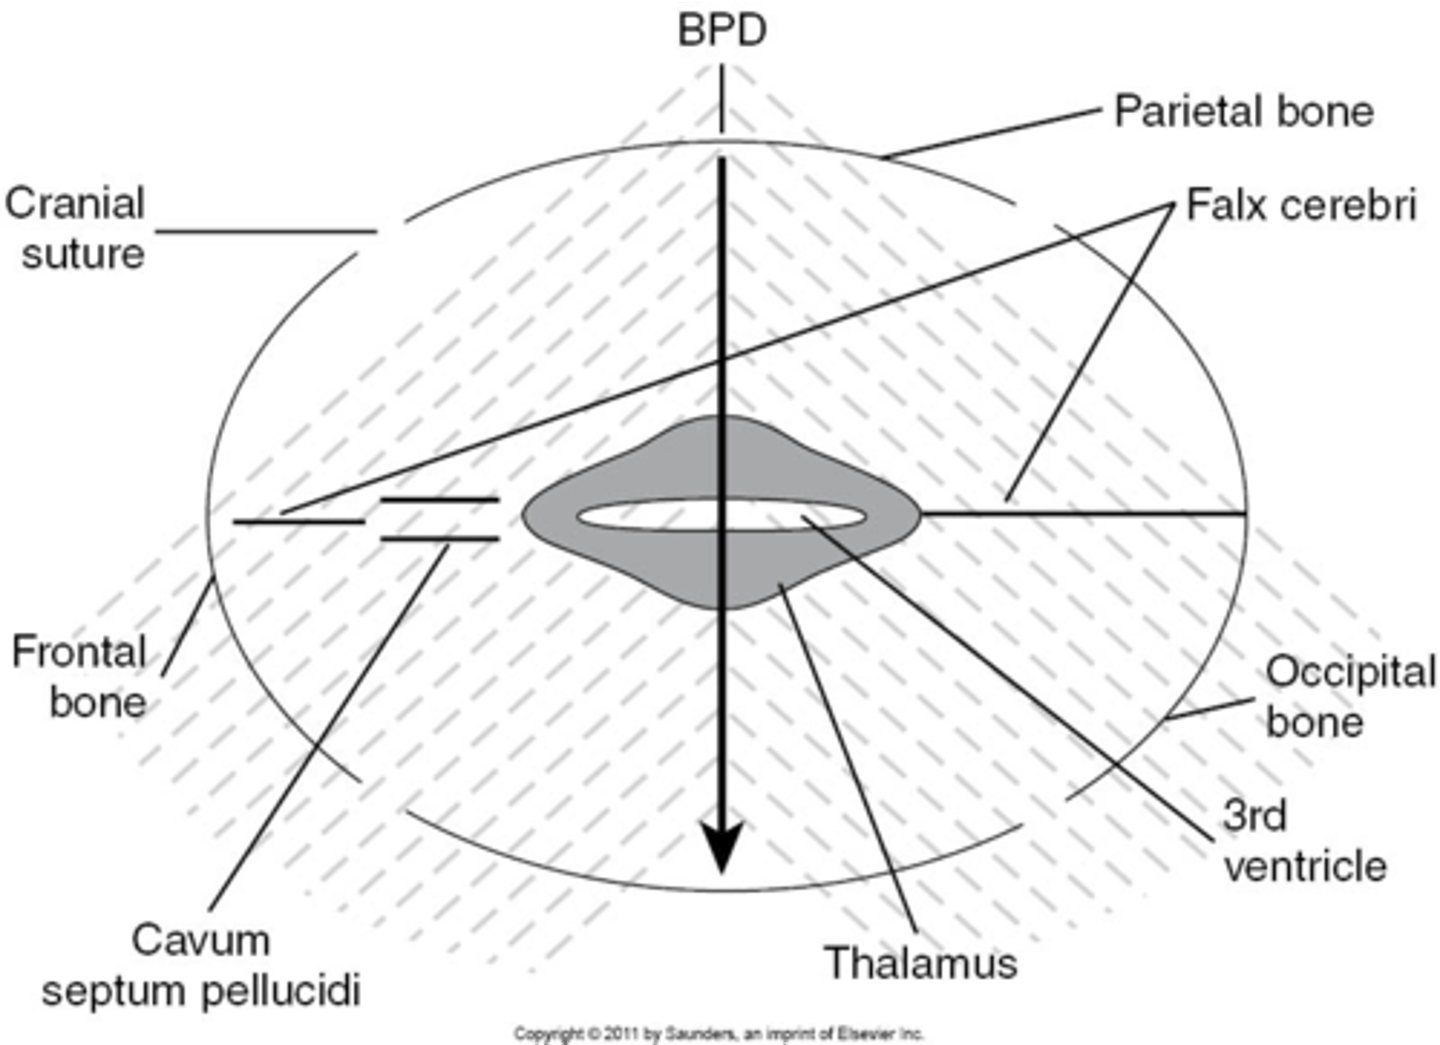

What is the most widely accepted means of measuring fetal head and estimating fetal age?

BPD

What part of the skull do you measure BPD?

midline echo complex

How do you find midline echo complex on ultrasound?

move the transducer caudally from lateral ventricles

When measuring BPD, paired ___ will be seen on either side

thalamus

When measuring BPD, what is located between the thalamus?

3rd ventricle